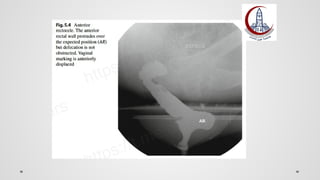

DEFECOGRAPHY

Spastic pelvic floor $